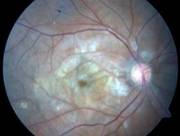

AMD |

(Vitamin supplements are not cures for AMD, nor can they restore vision already lost from AMD.)